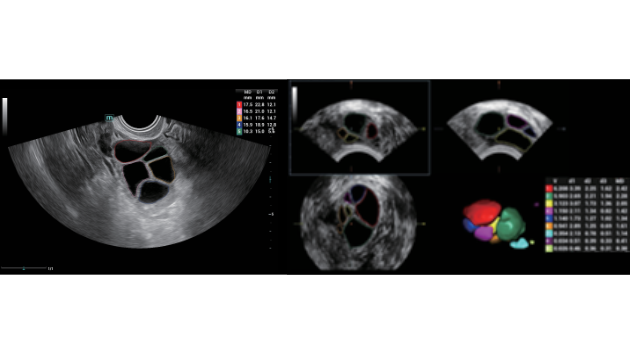

No matter your routine is in hospitals, clinics, or you are honing skills in General Imaging applications, women's health care or cardiovascular specialties, you will find highly powerful tools available on this series to keep you stay ahead.

Comprehensive Imaging Solutions Powered by ZST+

The ZST+ platform is an extraordinary innovation, representing an ultrasound evolution. Transforming ultrasound metrics from conventional beam-forming to channel data based processing. It overcomes the traditional trade-off limitation among spatial resolution, temporal resolution and tissue uniformity, delivering exceptional image quality for infinite imaging solutions with non-stop improvements.